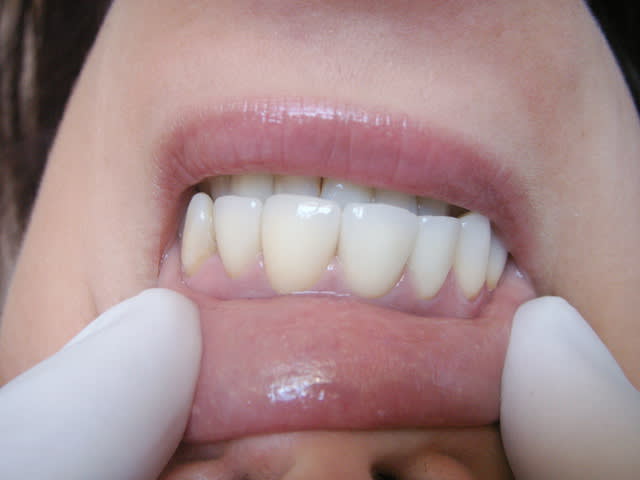

en haut, céram sur 13 et bridge / implants et en bas,

effectivement bridge sur implant, mais à partir de 44.

la patiente de 87 ans était super pressée d'avoir au moins une partie de terminée.

Dsc 3780 je8qkd - Eugenol

Dsc 3781 ud4ozj - Eugenol

Dsc 5836 sncbb0 - Eugenol

Dsc 5837 ch98nn - Eugenol

je suis bluffé!!!